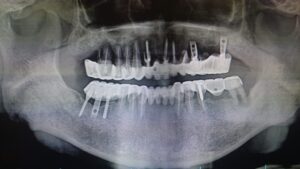

12年前に、長崎で治療したインプラントが、動き出して痛いから見てほしいとのことでした。

拝見してびっくりしたのは、最近ではまず見ない形のインプラントの形で、それもほとんど骨から浮いていた感じでした。

(CT撮影にて、診断)

(左下が弱っています。)